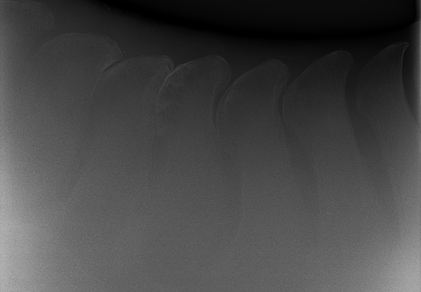

• Kissing Spines

• Röntgen zur Darstellung von Wirbelkörpern und den Dornfortsätzen

Röntgenbild eines Pferdes mit Kissing Spines